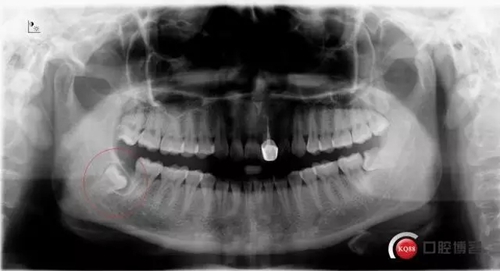

超低位阻生齒緊貼神經(jīng)管伴囊腫

術(shù)前曲面斷層